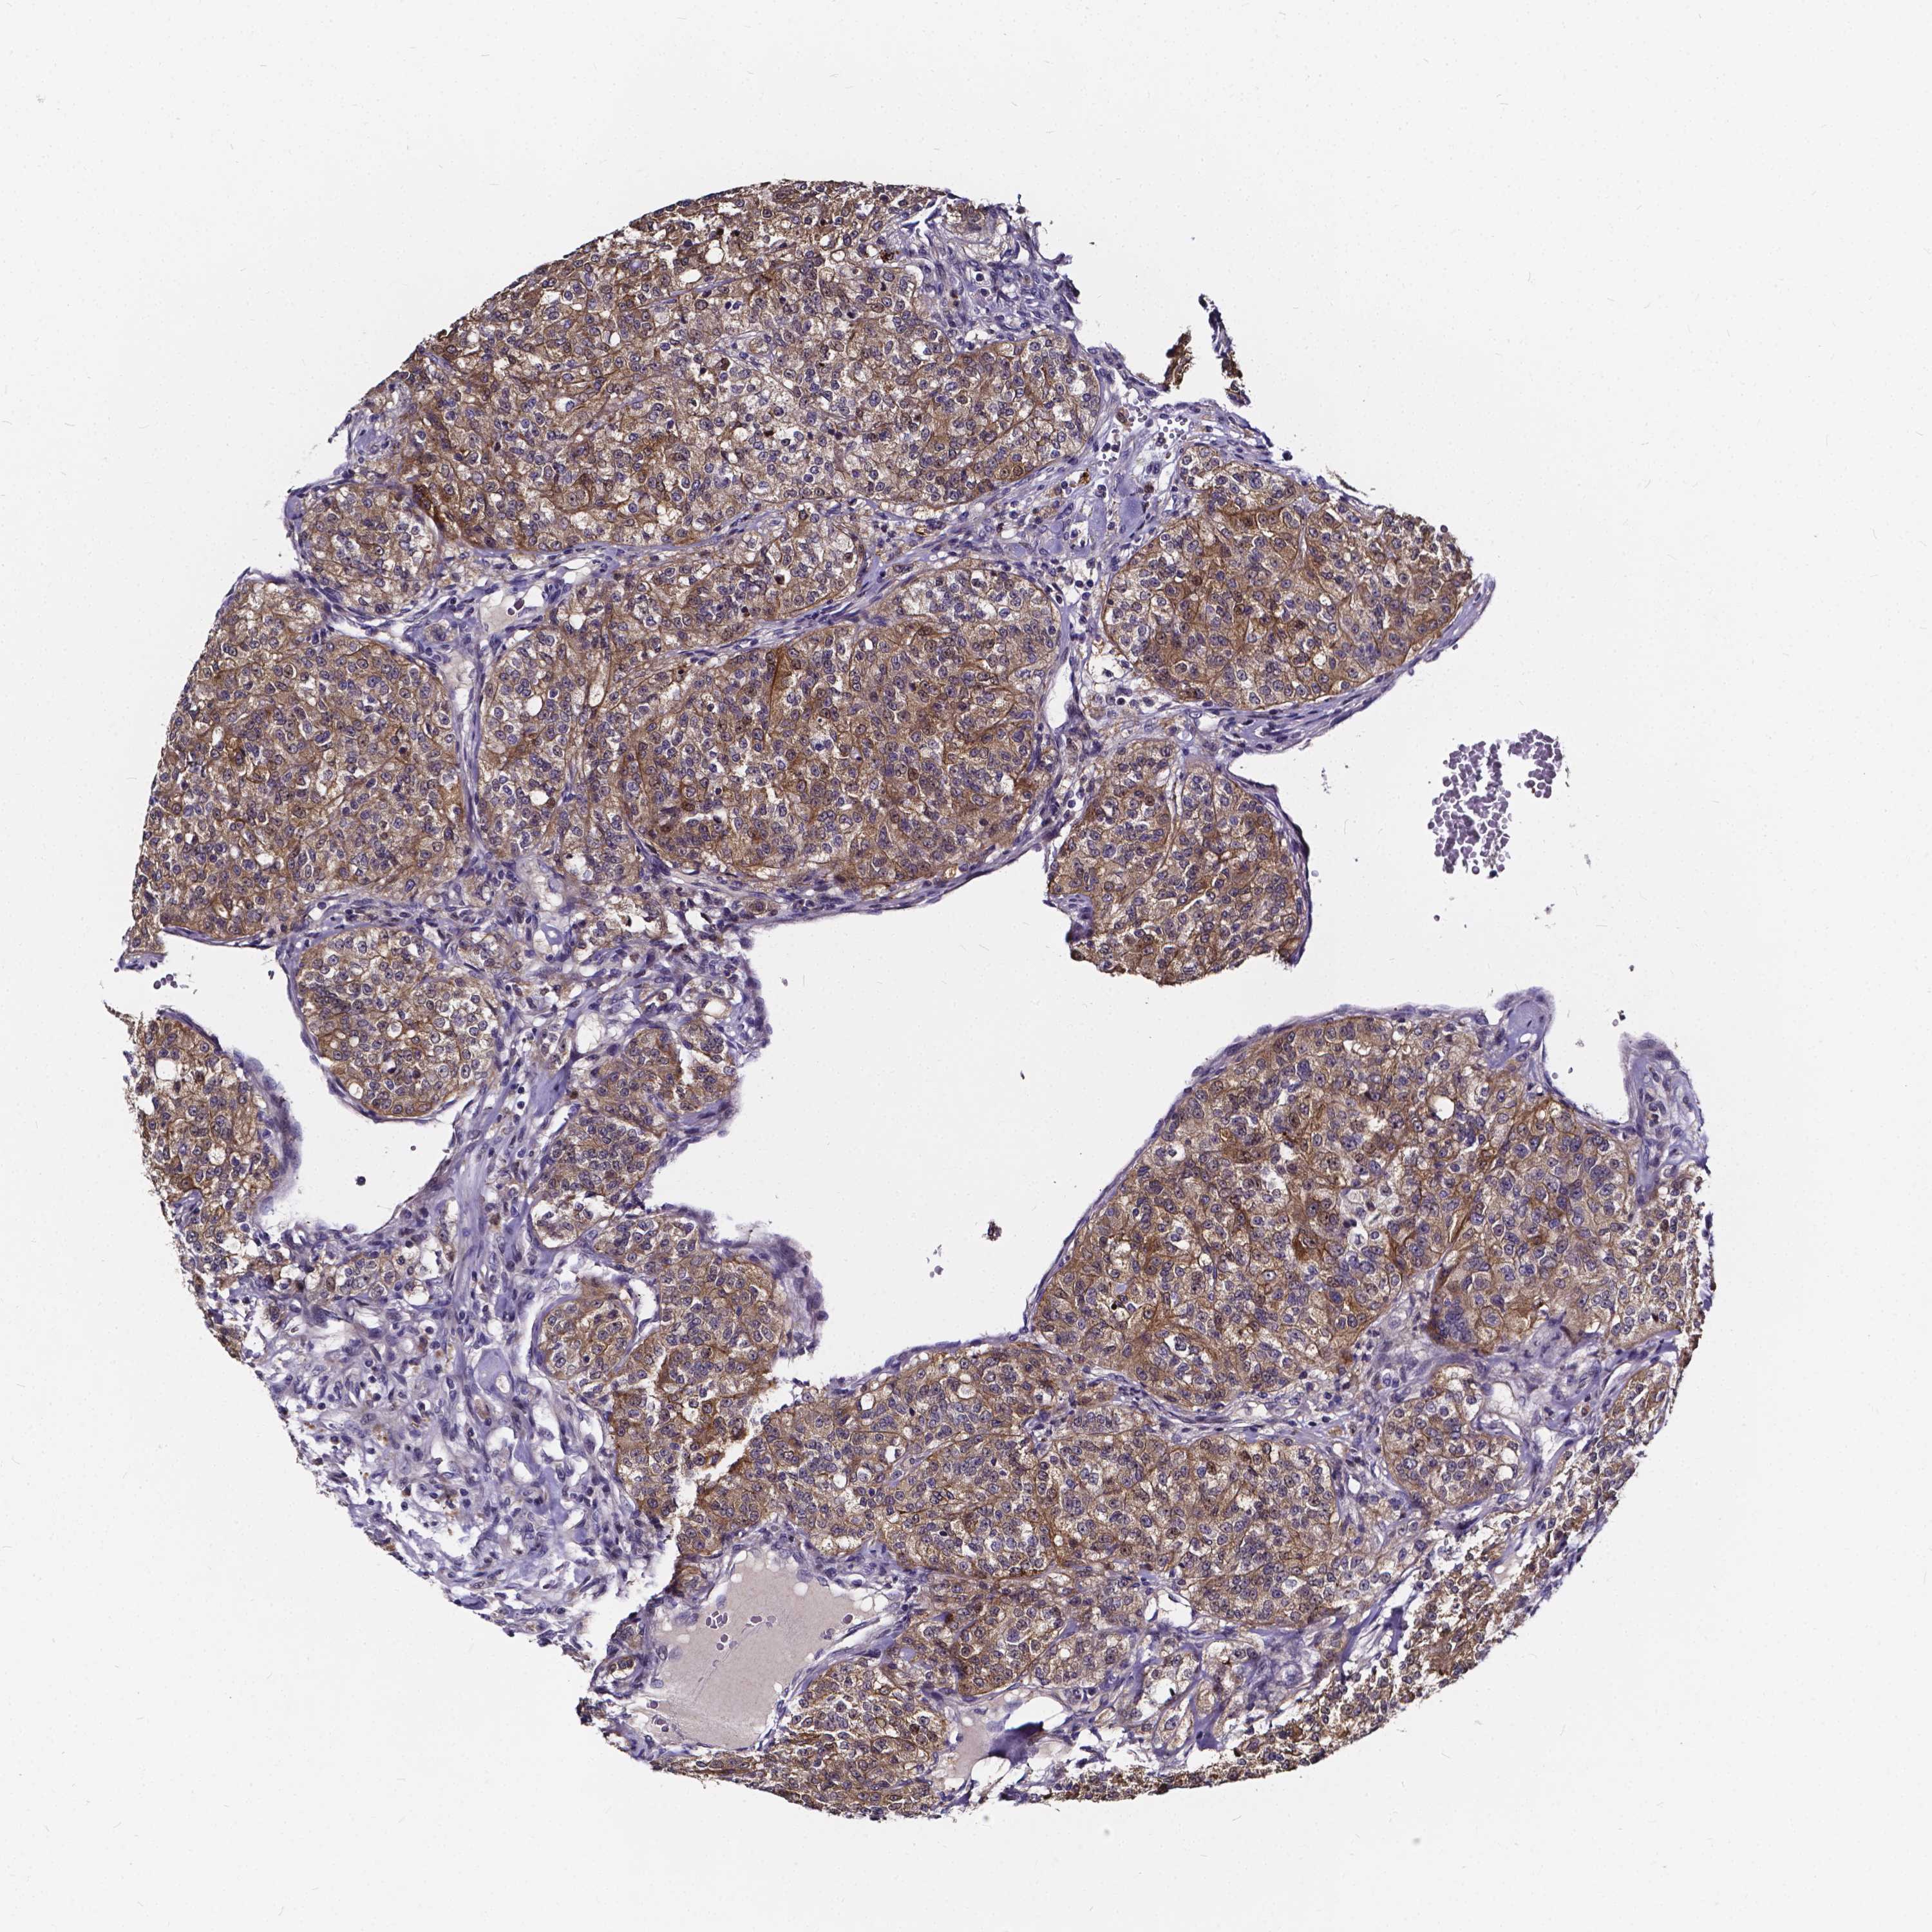

CANCER RENAL CANCER Show tissue menu

Renal cancer

Kidney renal clear cell carcinoma